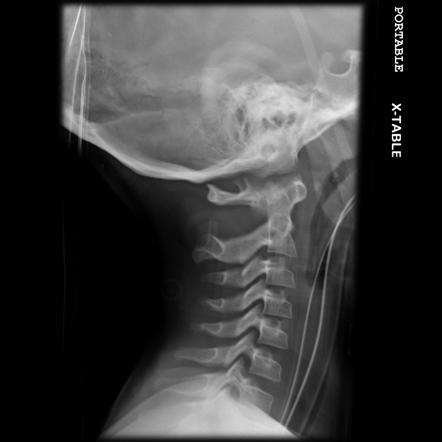

crashes. Motorcycle accidents are intrinsically dangerous; the police proverb says

“Buy Your son a motorcycle for his last birthday”. The individuals involved in

motorcycle injuries die of a head and neck injuries, the death is instant.